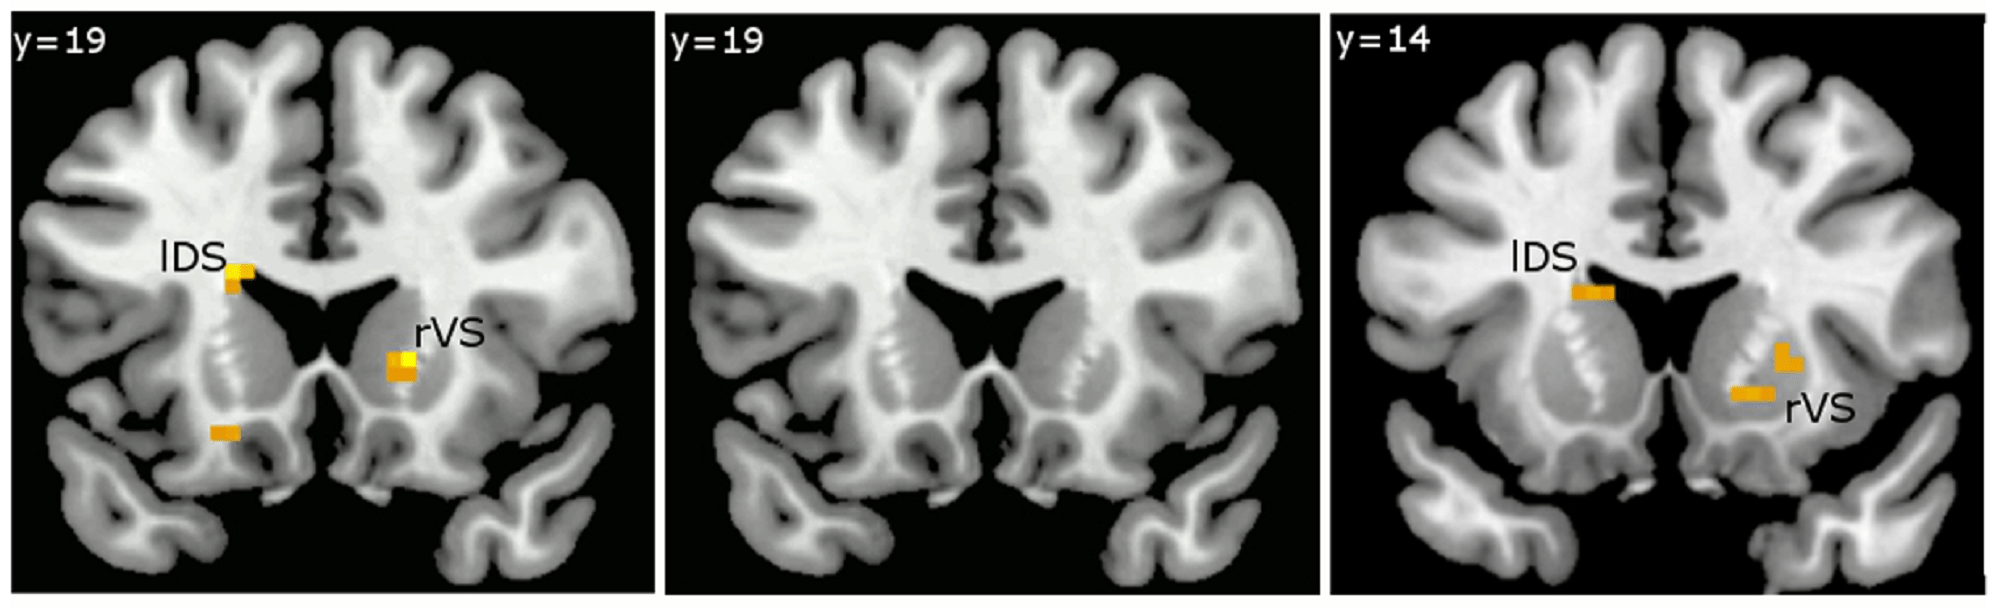

Pesquisa utiliza métodos de neuroimagem para investigar a relação entre o sistema cerebral de recompensa e o comportamento alimentar de...